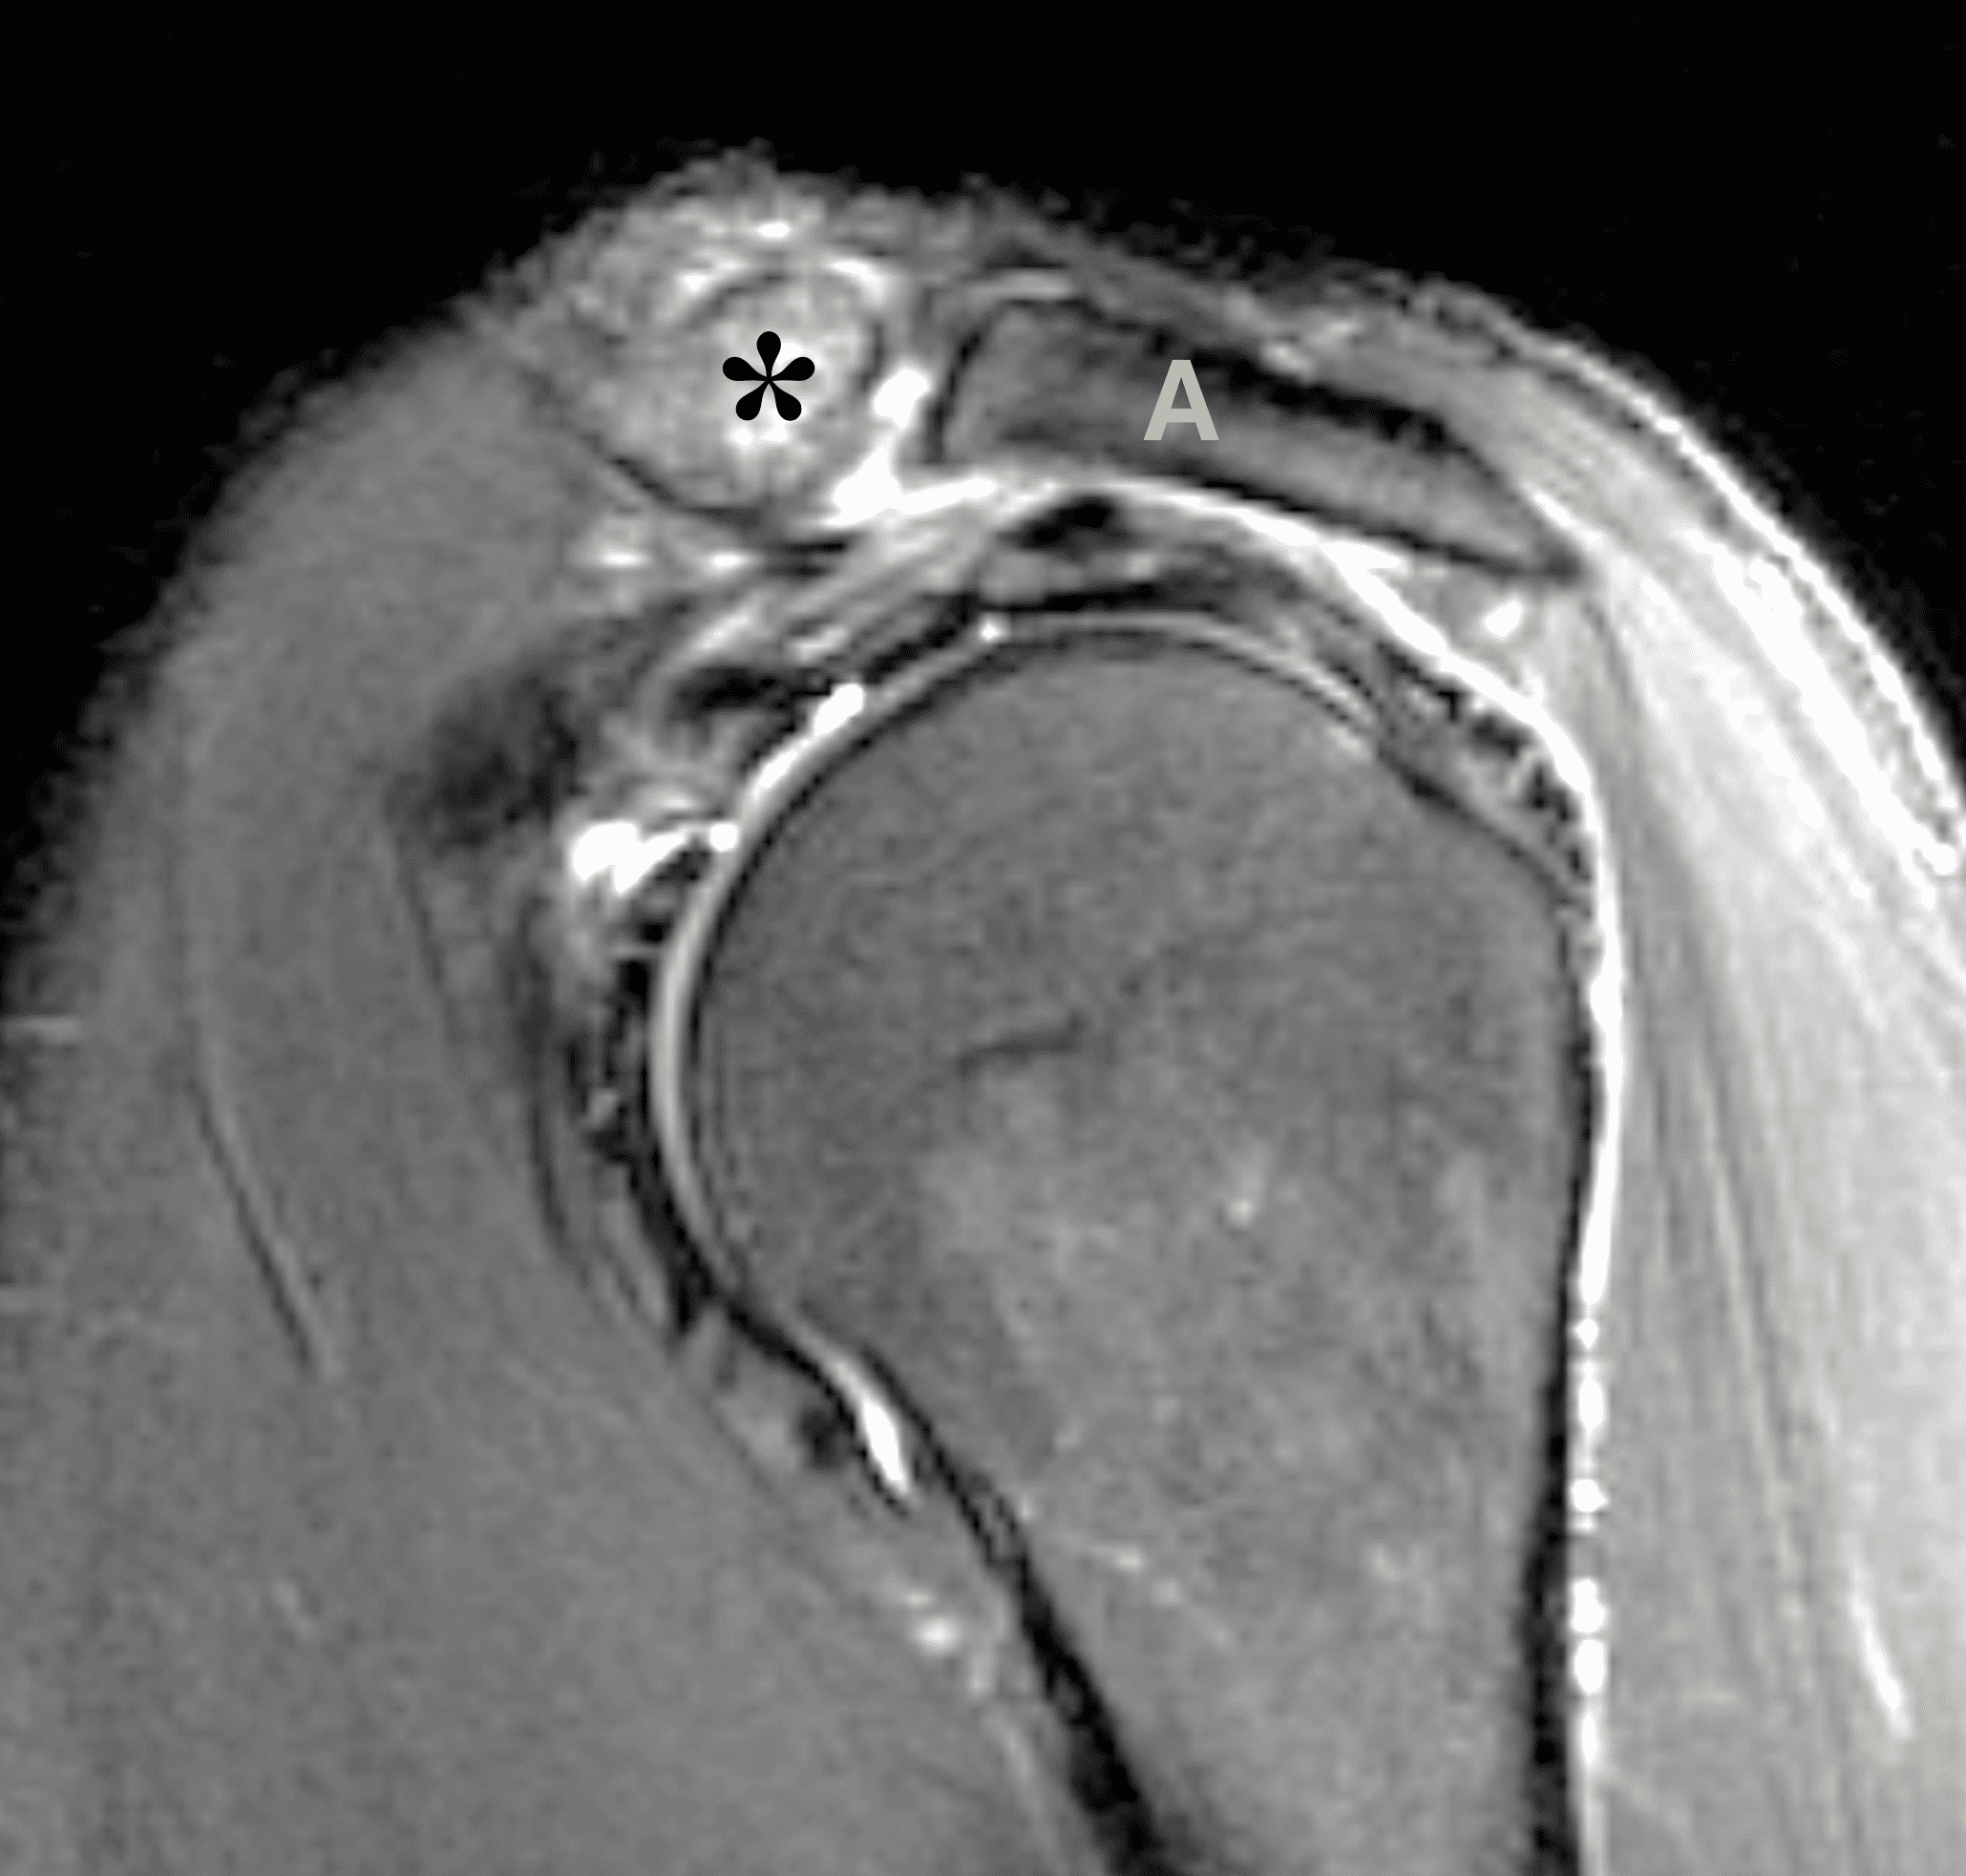

A 49-year-old male, avid weightlifter complains of chronic pain along the superior aspect of his right shoulder. He denies acute trauma. An AP radiograph (Figure 1A), as well as oblique coronal SPAIR (Figure 1B), axial fat-suppressed fluid sensitive (Figure 1C), and oblique sagittal T2-weighted images (Figure 1D) are shown. What are the findings? What is your diagnosis?

The principle MRI finding of DCO is distal clavicular marrow edema and surrounding inflammation on fluid-sensitive pulse sequences, especially with fat suppression (Figures 3 and 4).2, 9 Marrow changes can occur in patients with normal radiographs,10 in which case a term like “stress/overuse related marrow edema,” might be preferable to “osteolysis.” On MRI, more severe cases may show erosions or cysts in the distal clavicle and loss of the subchondral bone plate in addition to more pronounced marrow and soft tissue edema. A band of low signal paralleling the distal bone end may be present, suggesting a stress fracture line (Figure 5).8 However, a similar appearance can be due to the sclerotic rim surrounding distal clavicle cysts or small erosions (Figure 6). A small effusion or mild synovitis is often present in the AC joint.  Soft tissue edema within and surrounding the AC joint capsule and distal clavicular periosteum may be visible (Figure 3).  Some patients may also show marrow edema (or even erosions) in the anterior acromion, but the changes are typically more severe in the distal clavicle (Figures 5 and 7).2

While isolated DCO does not produce osteophytes, it may occur in patients with pre-existing osteoarthritis; in these cases, the marrow edema is typically out of proportion to the osteophytosis. When DCO occurs following an acute traumatic event like an AC joint separation, the MRI findings of that condition (e.g., widening or subluxation of the joint, disruption of the coracoclavicular ligaments) may be evident (Figure 8).1 Osteolysis can also develop following fractures of the distal clavicle, due to post-traumatic resorption of small, comminuted fracture fragments. In these cases, residual deformity of the clavicle or the presence of the original fracture lines may be evident on imaging studies. Additionally, because resorption of the fracture fragments typically occurs during the chronic healing after inflammation has resolved, marrow and soft tissue edema may not be present on MRI when the distal clavicular bone loss is seen.